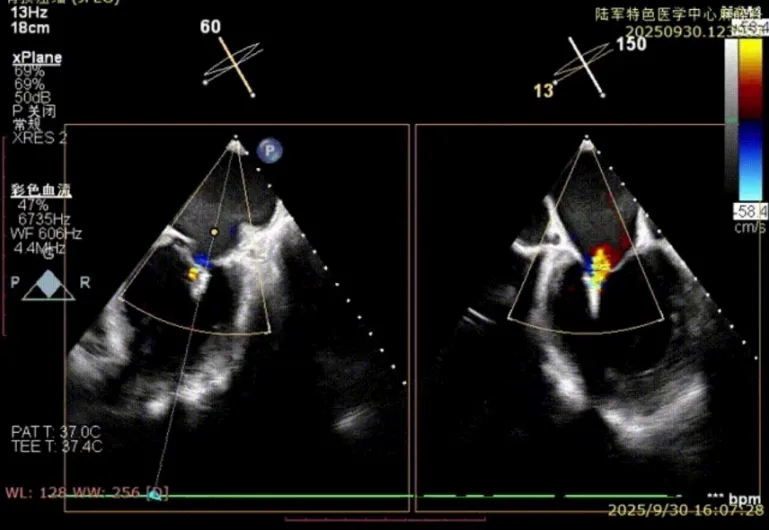

手术当日,吴庚泽副主任医师带领团队紧密配合,精细穿刺房间隔,精准定位瓣膜病变部位,成功完成夹合。术后即刻超声显示,患者二尖瓣反流由重度降至轻度,血压趋于稳定,室性心律失常消失,自觉症状显著缓解。患者顺利出院。